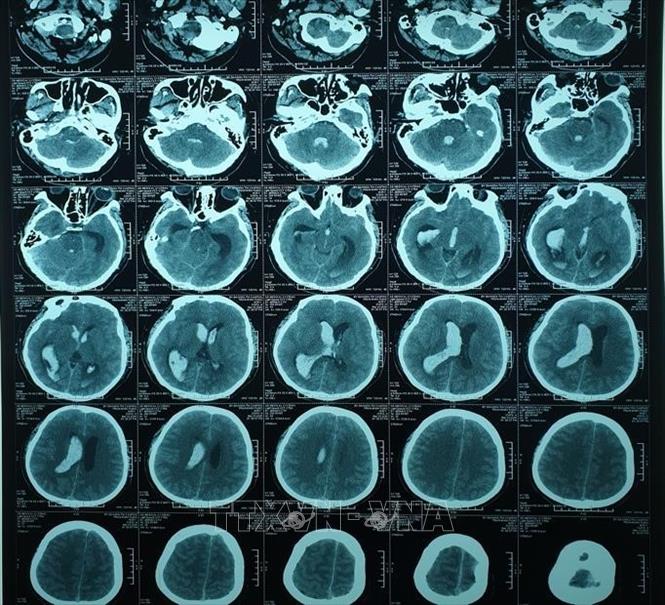

Hình ảnh chụp cắt lớp vi tính não bệnh nhân trước can thiệp. Ảnh: TTXVN phát

Kết quả chụp cắt lớp vi tính sọ não cho thấy bệnh nhân bị chảy máu não, tràn vào hệ thống não thất (những phần hốc, xoang chứa nước bên trong lớp xương sọ), gây dãn toàn bộ hệ thống não thất.

Hội chẩn đánh giá, các bác sỹ nhận định đây là ca bệnh nặng, nguy cơ tử vong gần như hoàn toàn nếu không xử trí kịp thời. Sau khi chụp hình mạch máu não để loại trừ nguyên nhân gây chảy máu, một ống thông dẫn lưu não thất ra ngoài đã được đặt, nhằm làm giảm áp lực nội sọ cho bệnh nhân. Kết quả chụp cắt lớp vi tính cho thấy hệ thống não thất đã bớt giãn nhưng vẫn còn tụ máu nhiều, khả năng tắc ống dẫn lưu là rất cao.